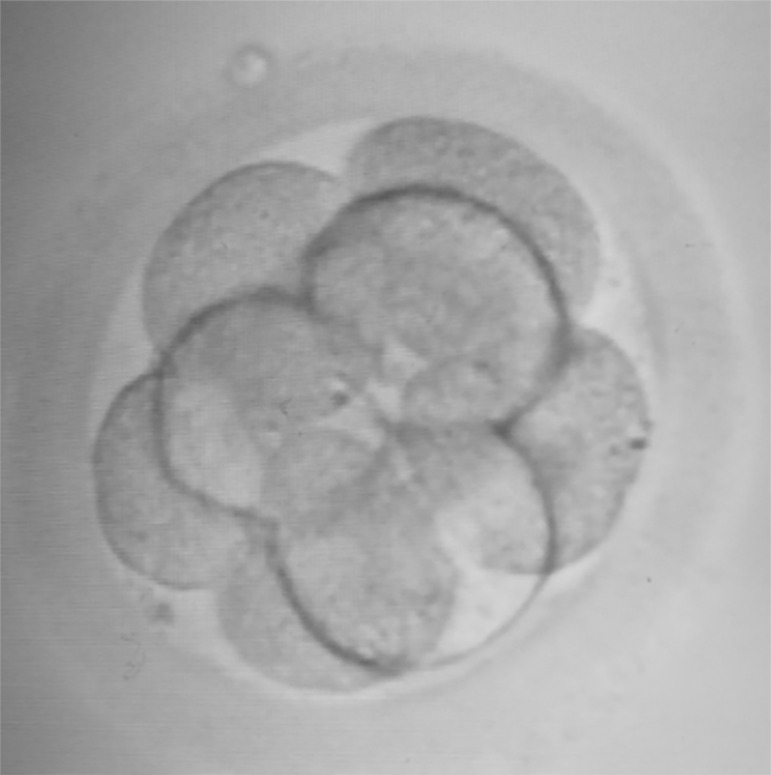

在本报告中,我们提出了一个不寻常的案例,一对夫妇通过ICSI成功怀孕,并收集了单个卵母细胞。卵母细胞复合体(COC)在触发后36.5小时被检索,发现处于II中期,在触发后约39小时进行精子注射。注射后18小时,单个卵母细胞受精,第2天发育为4细胞级胚胎,第3天发育为8细胞级胚胎,并将其放置在子宫腔中。妊娠结果为β-hCG阳性。在七周时进行的扫描显示,存在一个羊膜囊和胎儿心跳。正在进行的妊娠在妊娠24周时平安无事。

In this report, we present an unusual case of a couple who achieved a successful pregnancy by ICSI with a single oocyte collected. The cumulus-oocyte-complex (COC) was retrieved at 36.5 hours post trigger, and was found to be at metaphase II, when sperm injection was performed at around 39 hours post trigger. At 18 hours post injection, the single oocyte was fertilized, developed to four-cell embryo on day 2, and 8-cell grade on day 3, when it was relocated in the uterine cavity. The pregnancy yielded a positive β-hCG result. The scan performed at seven weeks, revealed the presence of one amniotic sac with a fetal heartbeat. The ongoing pregnancy has been eventless at 24 weeks of gestation.